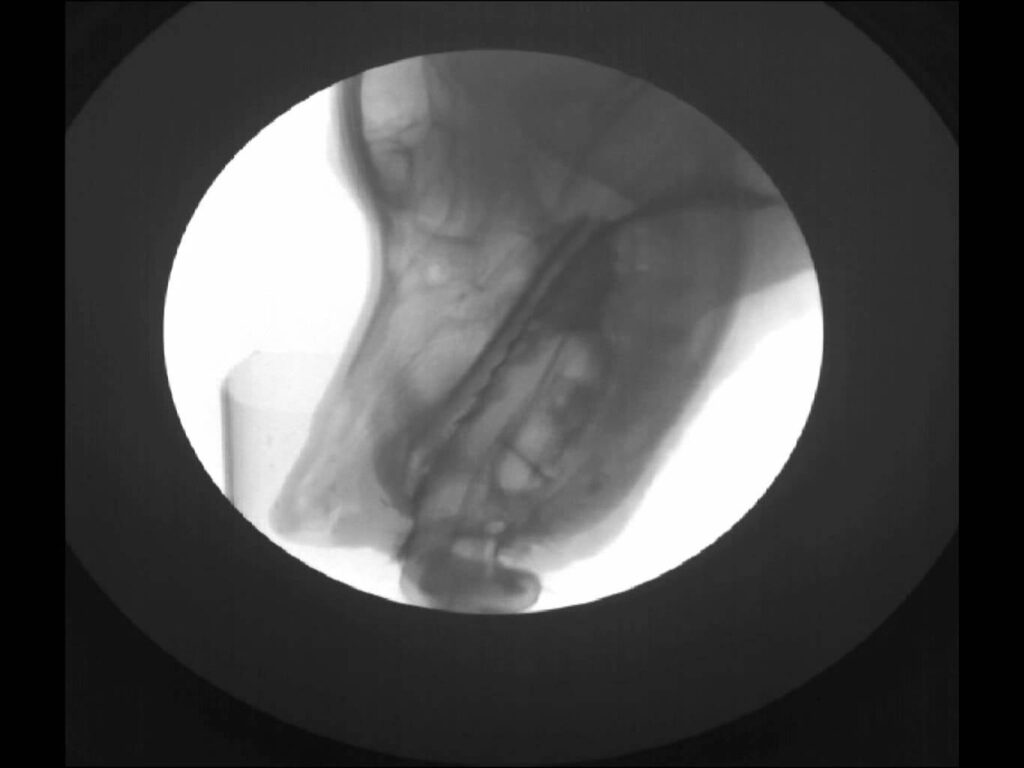

¿Alguna vez has visto un gato por dentro? No, no hace falta que diseccionemos al pobre minino ni lo sedemos para meterlo en una máquina de rayos x. Basta con esperar a que el gatito pase por delante del sensor de un fluoroscopio para obtener imágenes tan increíbles como esta. Pero ¿Qué es un fluoroscopio?…